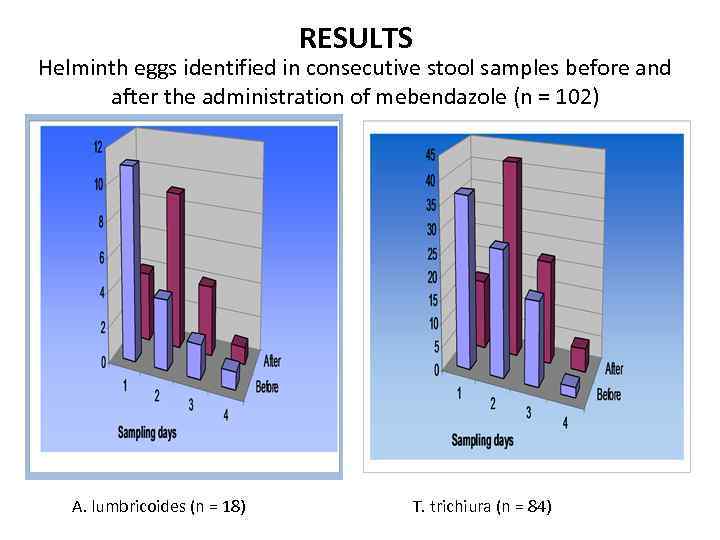

STUDY DESIGN In a cohort (n=240) randomly selected from consecutive out-patients (n=300) with symptoms and signs of chronic gastrointestinal conditions, ascariasis and trichuriasis were diagnosed. Those patients were treated with mebendazole (100 mg twice a day for 3 days).

STUDY DESIGN On a follow-up examination 3 to 6 weeks after therapy, 102 patients were still found to have gastrointestinal conditions. The same parasitic infections were diagnosed by stool microscopy over 4 consecutive days on the follow-up assessment.

RESULTS Helminth eggs identified in consecutive stool samples before and after the administration of mebendazole (n = 102) A. lumbricoides (n = 18) T. trichiura (n = 84)